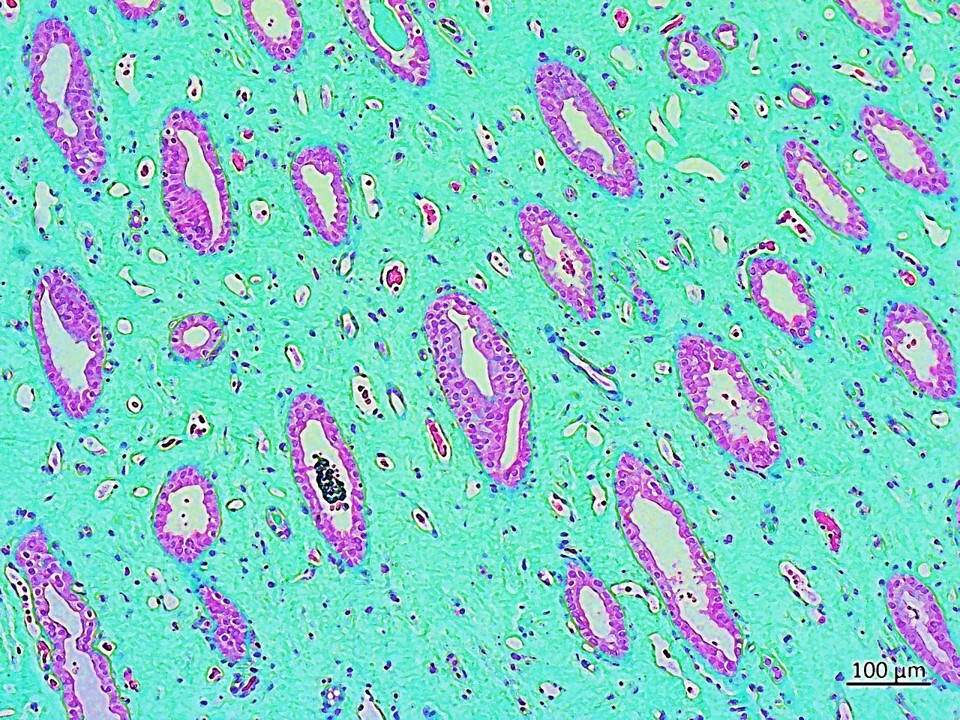

The hypothetical presence of a biological switch that can turn on/off at the onset of hypoxia in the renal papillary tip region of stone formers is a new concept that can be determined at the biomolecular level with first-principles investigations. For example, the hypoxia inducible factor 1α (HIF1α) is associated with progressive oxidative stress-related chronic renal injuries, tissue fibrosis and genetic expressions of vimentin – a biomarker of epithelial-to-mesenchymal transitions [Higgins 2007]. The expression of vimentin and other pathological biomarkers of fibrosis such as collagen and calcium deposits were detected with histology studies of the renal tip of clinical stone-former patient samples, to subsequently inform the development of functional assays on a chip, to investigate similar biomarkers of interest (Figure 9) [ Jeewandara 2023, ref 47].

Using histology sections for analyses with an artificial neural network derived from quantitative pathology (quPath) software, I first measured the key biomarkers of renal calcification, and these outcomes guided the subsequent development of organ-on-a-chip functional assays. In detail, the epithelial-to-mesenchymal transitions visualized with vimentin-DAB are a precursor of fibrosis and subsequent calcification, the biomarker was significantly expressed in renal stone forming patient samples (SF) compared to non-stone formers (NSF). Collagen is another biomarker of renal injury and fibrosis that we visualized with Masson's trichrome for quantification, upregulated in the renal papillary region due to shear stress. Stone forming patients showed significantly higher levels of collagen deposition vs. non-stone formers. We used the Alizarin red dye to visualize and identify renal calcification, where calcium deposits appeared as crimson aggregates across the tissue. As expected, renal stone-formers showed higher levels of calcium deposits due to dye uptake compared to NSF. In our study, the papillary tip region of all stone-forming patient samples exhibited the key biomarkers of collagen deposition (Masson's Trichrome), epithelial-mesenchymal transitions (vimentin-DAB), and calcification (Alizarin Red) in greater quantity than non-stone formers (Figure 9) [Jeewandara 2023].

The region of interest: the renal papillary tip A) The human renal papillary tip region (from L-to-R) stained with DAB-Vimentin antibody to demonstrate epithelial-to-mesenchymal transitions during renal fibrosis, followed by trichrome stains to indicate collagen deposition and renal fibrosis, and alizarin red to identify calcium deposits (red). B) Histology-stained renal papillary tips were quantified with an artificial neural network by using quPath software to measure regions of interest a) vimentin for endothelial-mesenchymal transitions, b) the ANN-driven segmentation method represented with Alizarin red dye during renal calcification and quantification, and c) Masson’s trichrome stained collagen area, d) log values of the multivariate analyses of all samples across the renal papillary cross-sections. Image credit: Author’s own.

The histology work also delineated the significantly upregulated expression of pathological biomarkers of renal fibrosis, epithelial-mesenchymal transitions, and subsequent calcification represented via collagen deposits, vimentin, and alizarin red dye deposits, respectively, in stone forming patients to be greater than in non-stone forming patients. The results presented herein are only a snippet of the completed mechanobiology and biomolecular project to emulate biomarkers of renal calcification; through bottom-up engineering a pathological cascade on an organ-chip instrument. Future articles will include further iterations of the completed research works.